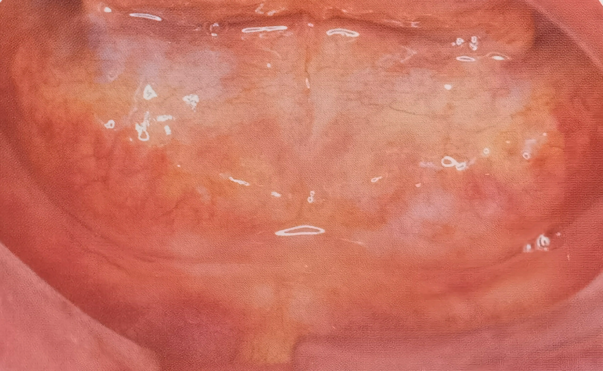

一类

二类

三类

四类

图3.一类至四类无牙合口内像